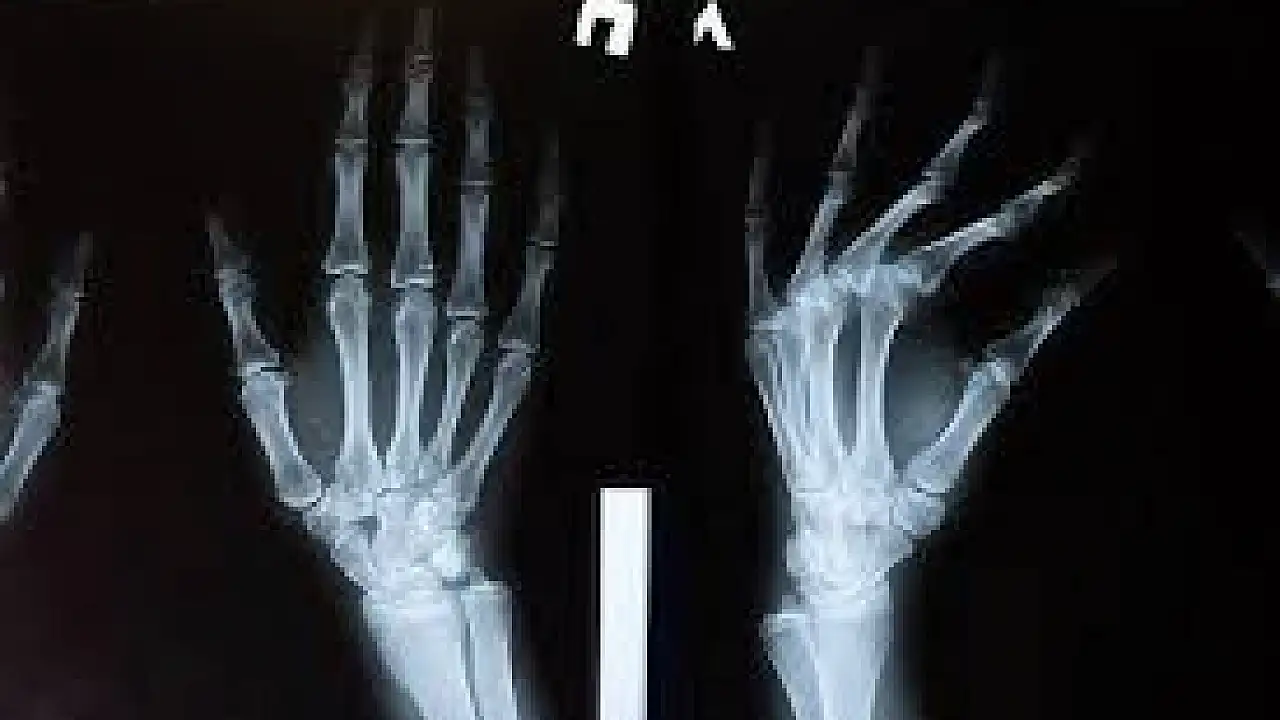

Yıllar boyunca parmak eklemlerini çıtlatmanın eklem etrafındaki kıkırdağa zarar vereceği yaygın bir kanı olmakla birlikte, aslında bu konuda fazla delil bulunmuyor.

1990’da Detroit’te yapılan daha geniş kapsamlı bir araştırmada da 45 yaş üstü 300 kişinin elleri incelendi. Parmak çıtlatanların yüzde 84’ünün ellerinde şişme belirtilerinin yanı sıra bir şey tutarken daha güçsüz oldukları görüldü. Araştırmacılar bu nedenle parmak çıtlatmada caydırıcı olmak gerektiği sonucuna vardı.

O halde parmak çıtlatma ile eklem hastalıkları bağlantısı nasıl kuruluyor? Artrit hastalığı olanların eklemlerindeki kıkırdak hasarlı olduğu için arada bir parmakları kendiliğinden çıtlar. Ama bu hasarın nedeni değil, sonucudur. Artritin nedenleri arasında yaşlılık, genetik faktör, elin incinmesi, ömür boyu elle ağır iş yapılması gibi etkenler sıralanıyor.